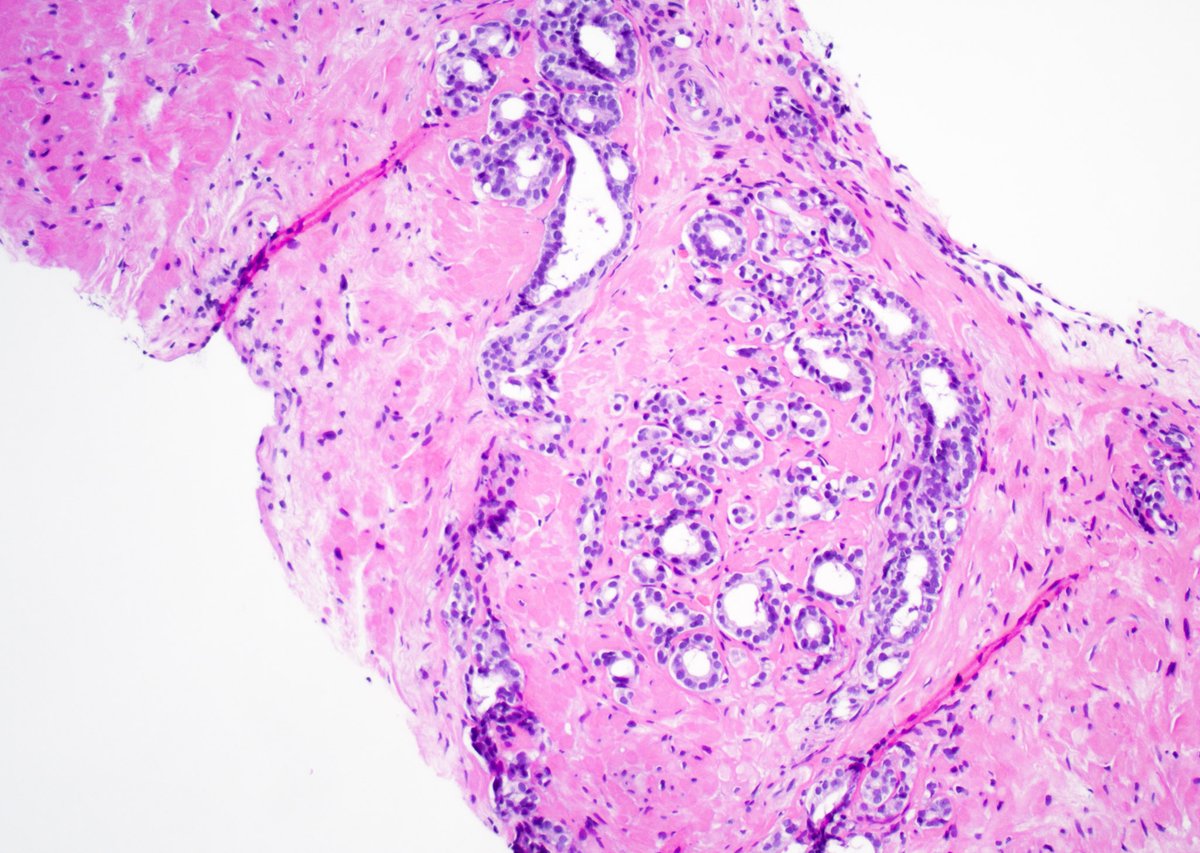

HER2 interpretation is increasingly complex—with evolving definitions come real challenges, especially reproducibility. We’ll cover navigating HER2-low & ultralow in a clinically meaningful way.